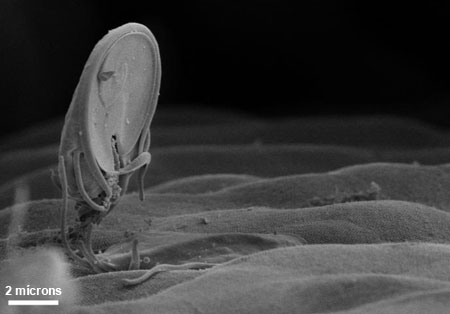

Giardíase

Micrografia eletrônica por varredura do trofozoíto da giárdia na superfície da mucosa do intestino. O disco adesivo ventral, que facilita a adesão à superfície intestinal, pode ser observado na parte inferior do microrganismo

Cortesia de Dr Stan Erlandsen; CDC Public Health Image Library (PHIL)